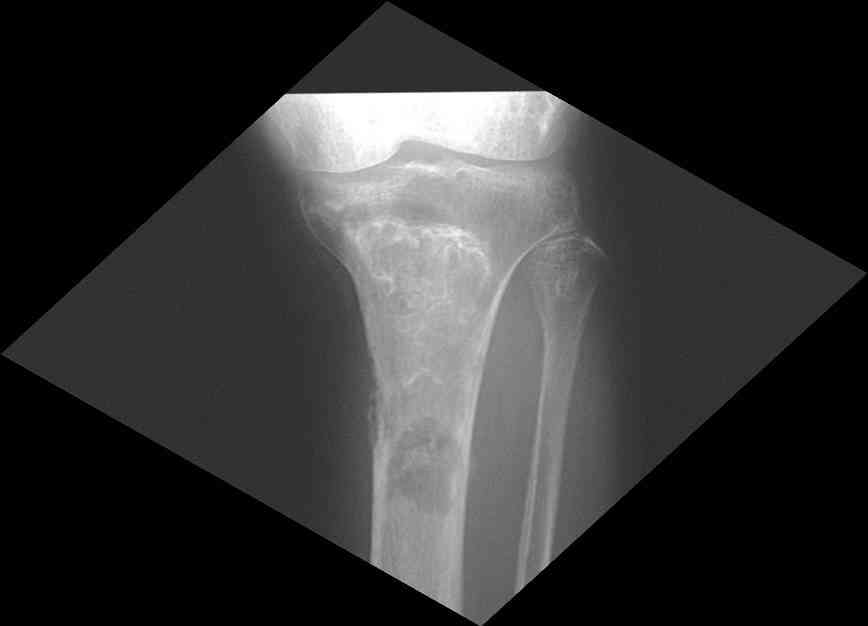

Изменения структуры костей у Вашего пациента больше похожи на

полиоссальную форму фиброзной дисплазии или болезнь Педжета, возможены

также инфаркты костного мозга б.берцовых костей. К сожалению, качество

снимка не очень хорошее, не понятно, сохранен ли кортикальный слой

б.берцовых костей по передней поверхности.

Для примера привожу случай из архива американской ассоциации

рентгенологов (ACR) - развитие злокачественной фиброзной гистиоцитомы

на левой б.берцовой кости у пациента с множественными инфарктами

костного мозга (рис 4,5 - левая, рис 6 - правая)